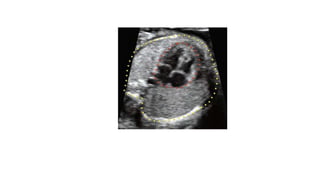

• #17 Schematic drawing and apical four-chamber view (B) with a highlight of the left ventricle (LV) (C) and right ventricle (RV) (D) in a normal fetus, showing the differentiating features of the LV and RV. The LV is longer than the RV (double-sided arrows), is smooth, and forms the apex of the heart (yellow arrow). The RV is coarse and has the typical moderator band (white arrow) in its apex. The tricuspid valve (TV) is shown to insert more apically on the septum than the mitral valve (MV).